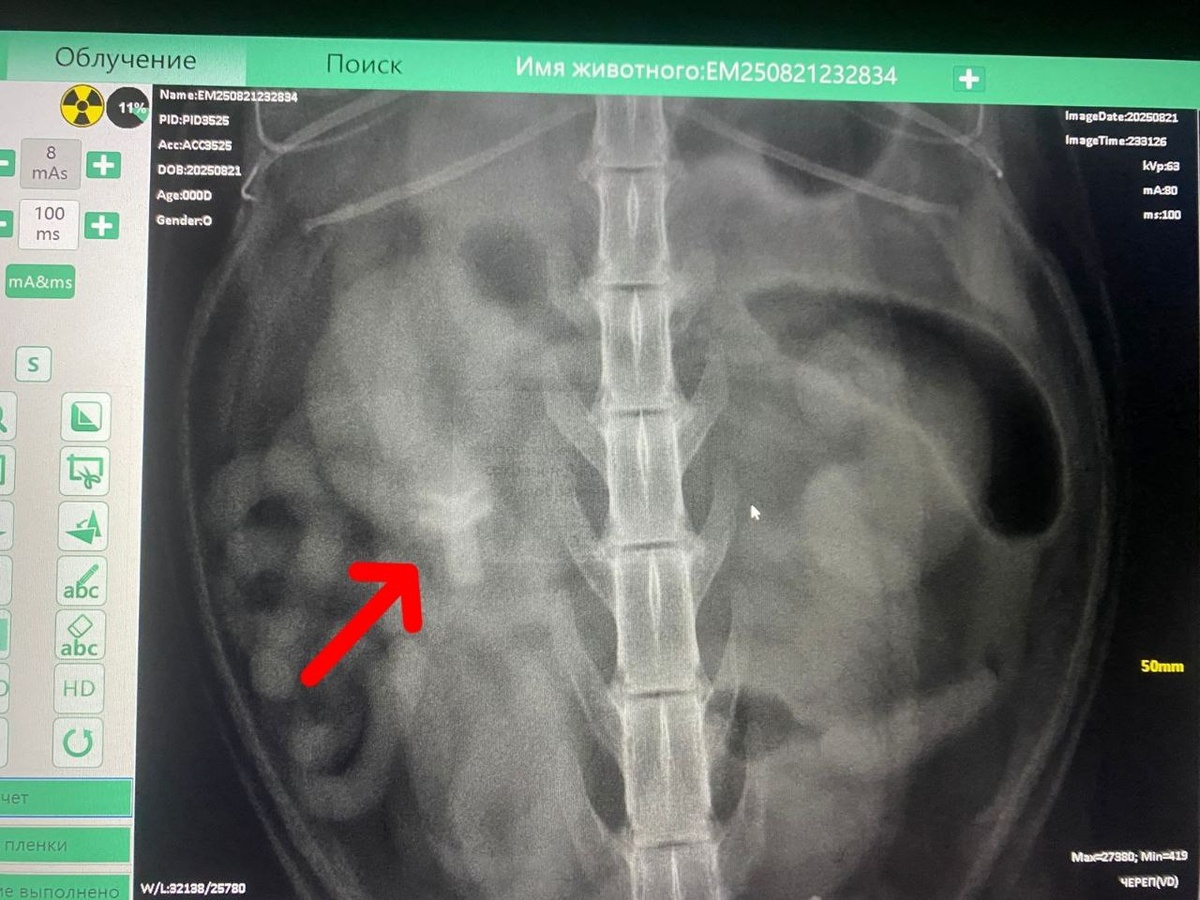

Ох уж эти котики! Тянут всякое в рот, как малые дети 👶👶🍼 Вот такой инородный предмет был обнаружен на рентгене. ❗Наши врачи провели срочную операцию, предмет извлекли (листайте карусель) Без него котику стало явно лучше 😉

Вот такой инородный предмет был обнаружен на рентгене.